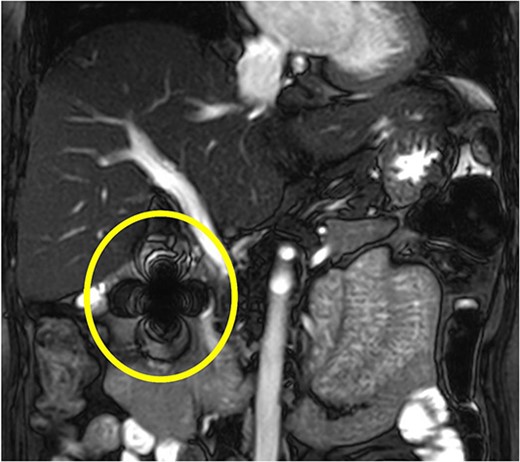

Magnetic resonance cholangiopancreatography (MRCP) was performed to determine the relationship between the foreign body and the main pancreatic duct. MRCP showed a severe ferromagnetic artifact in the pancreatic head and the second part of the duodenum, suggesting the presence of a metal foreign body in that area (Fig. 3). After MRCP findings, the patient disclosed that she had received acupuncture therapy from an acupuncturist at a Korean Oriental medical clinic for back pain 3 months earlier. She was referred to our department for the surgical treatment of chronic cholecystitis and a pancreatic foreign body. Hence, an elective laparoscopic surgery was performed.

MRCP shows a severe ferromagnetic artifact in the pancreatic head and the second part of the duodenum, suggesting the presence of a metal foreign body in that area.